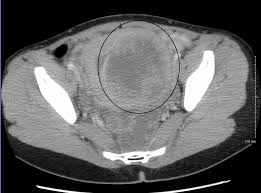

First described by Richet in 1857 the symptoms of chronic dull pelvic pain pressure and heaviness are often a result of dilated tortuous and congested veins produced by retrograde flow through incompetent valves in ovarian veins 39 41 Fig 18. Pelvic congestion syndrome PCS is characterized by chronic pelvic discomfort exacerbated by prolonged standing and coitus in women who have periovarian varicosities on imaging studies. It is thought to be caused by problems with the veins in the pelvic area.

Pelvic Congestion Syndrome Radiology Key